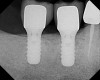

Approximately 18 weeks following extraction and grafting, full-thickness flaps were reflected, revealing complete osseous regeneration of the original defect (Figure 8). The osteotomy was initiated with the same trephine bur to harvest a core of representative bone present at the site of implant insertion. Implant placement proceeded without alteration from the manufacturer's protocol by inserting a 4.8-mm x 8-mm fixture with primary, tactile, stability, and transmucosal healing properties. At about 8 months postplacement, the implant was restored with a custom abutment and cement-retained crown (Figure 9).

Figure 9  Radiographic appearance of restored implant.

Figure 9

Figure 13  Radiograph at time of restoration of two separate implants, with cement-retained crowns and healthy proximal bone levels.

Figure 13